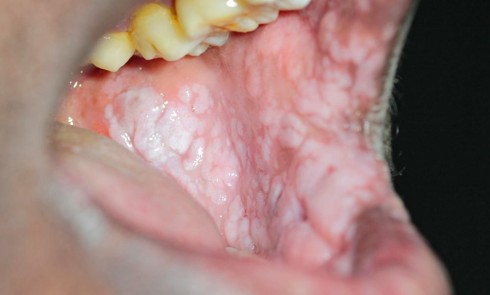

Anamnèse Une patiente de 29 ans, sans antécédent médical rapporté et non-fumeuse, consulte pour une inflammation gingivale persistante, malgré plusieurs...